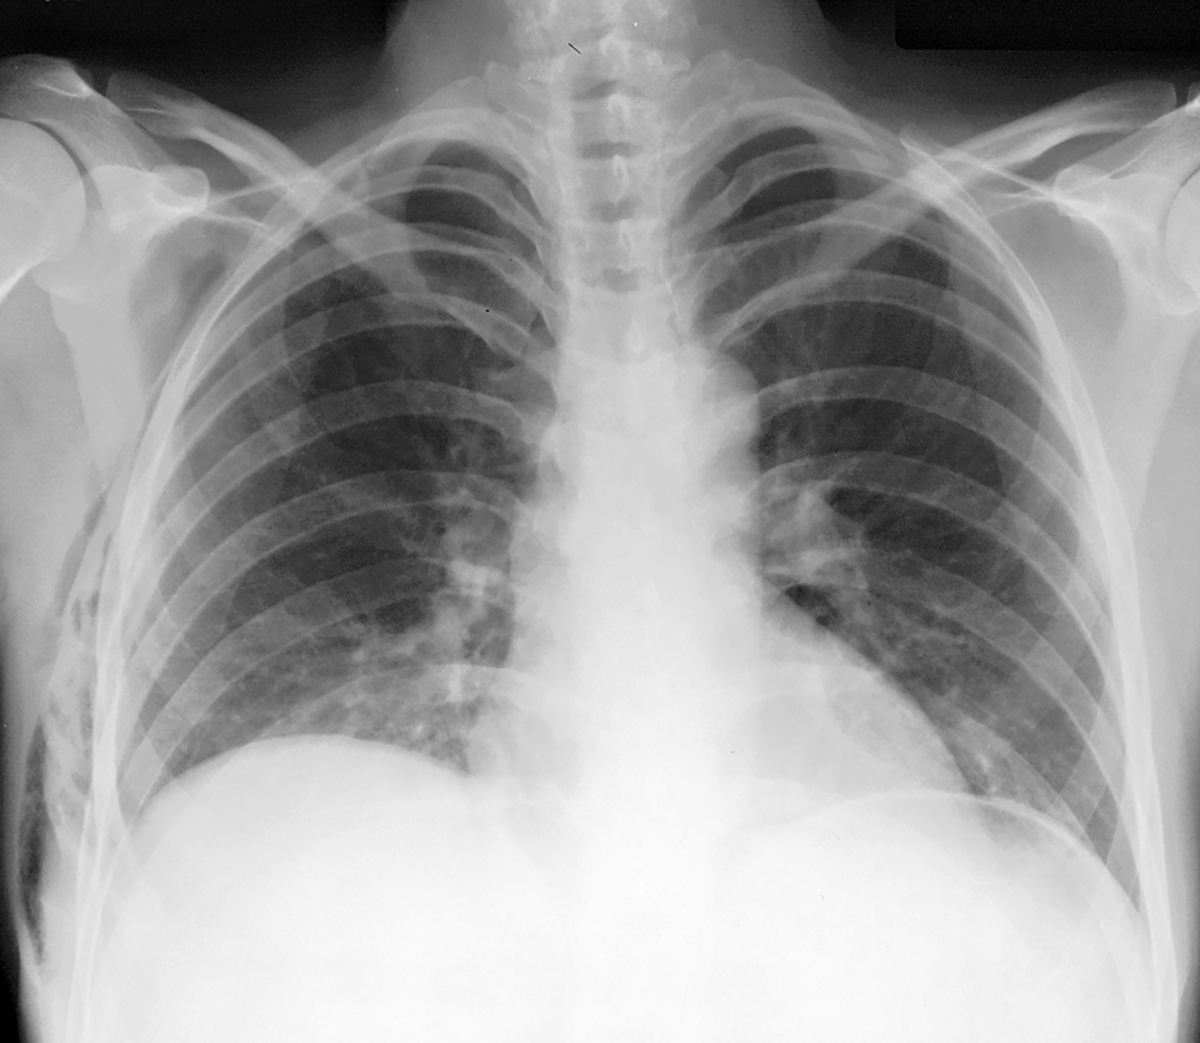

advanced case for other abnormal air